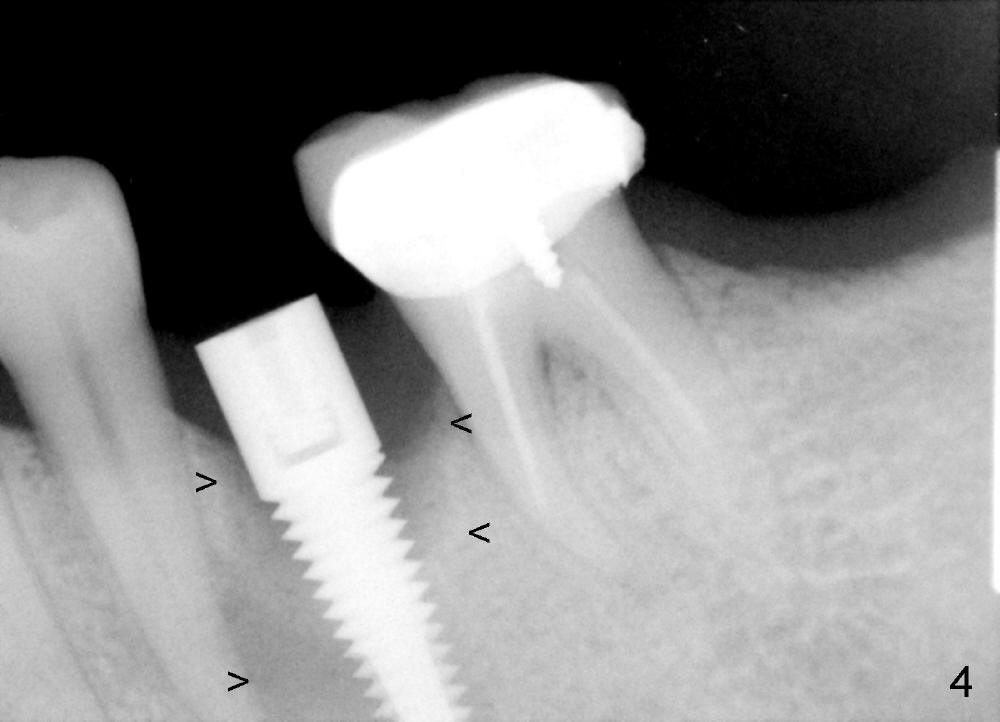

A 44-year-old lady has poor dentition. The tooth #20 has a residual root (Fig.1 R). Immediately after extraction, osteotomy is formed by drills (Fig.2: 3.5x17 mm); a 4.5x17 mm implant is placed (Fig.3 (arrowheads: boundary of the socket)). The patient returns 9 months later with increased radiolucency around the implant (Fig.4) and buccal swelling (Fig.5, asymptomatic). Raising the buccal flap confirms bone loss around the implant (Fig.6). Following debridement, allograft is placed. The source of the infection is unknown.